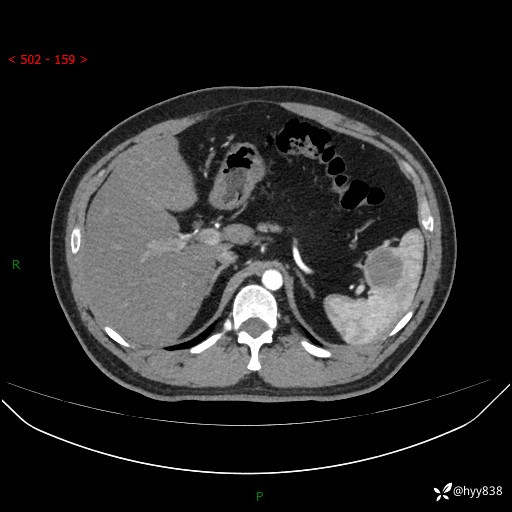

【患者信息】:31岁/男

【主诉】:超声发现脾脏肿物,为进一步诊治来我院,门诊以“脾脏占位”收入院

【检查】:上腹部CT平扫+增强